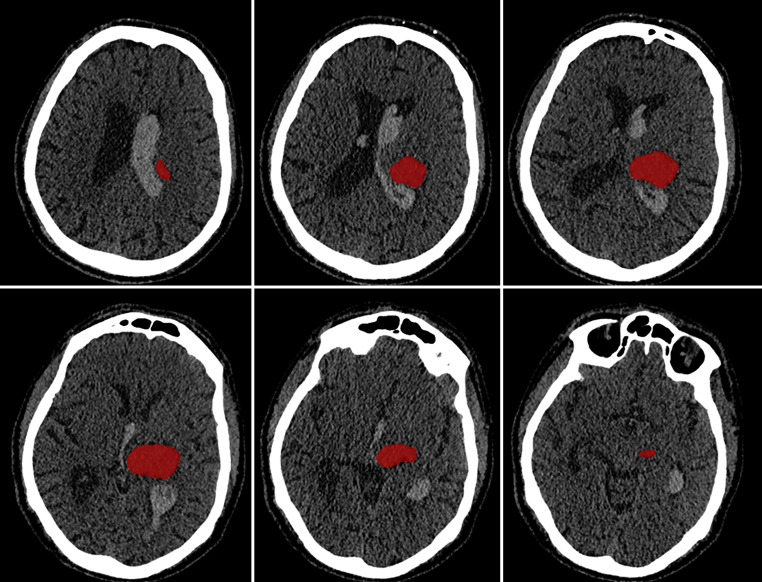

Methods: Our retrospective analysis included 322 ICH patients. We defined myocardial injury as an elevation of hs-cTnT above the 99th percentile (i.e. 14 ng/L). Acute myocardial injury was defined as either a changing pattern of > 50% within 24 h or an excessive elevation of initial hs-cTnT (> 52 ng/L). 3D brain scans were assessed for ICH visually and quantitatively by a deep learning algorithm. Multiple regression models and Voxel-based Lesion-Symptom Mapping (VLSM) were applied.

Results: 63.0% (203/322) of patients presented with myocardial injury, which was associated with more severe strokes and worse outcomes during the in-hospital phase (P < 0.01). Acute myocardial injury occurred in 24.5% (79/322) of patients. The only imaging finding associated with acute myocardial injury was midline shift (69.8% vs. 44.6% for normal or stable hs-cTnT, P < 0.01), which also independently predicted it (odds ratio 3.29, confidence interval 1.38-7.87, P < 0.01). In contrast, VLSM did not identify any specific brain region significantly associated with acute myocardial injury. Acute myocardial injury did not correlate with preexisting cardiac diseases; however, the frequency of adverse cardiac events was higher in the acute myocardial injury group (11.4% vs. 4.1% in patients with normal and/or stable patterns of hs-cTnT, P < 0.05).